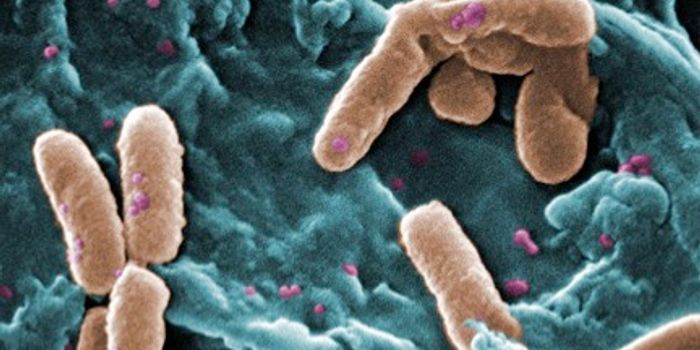

OCT 27, 2017Clinical & Molecular DXMadagascar is currently battling a plague outbreak that has so far infected nearly 1,200 people and killed 124 people. I ...